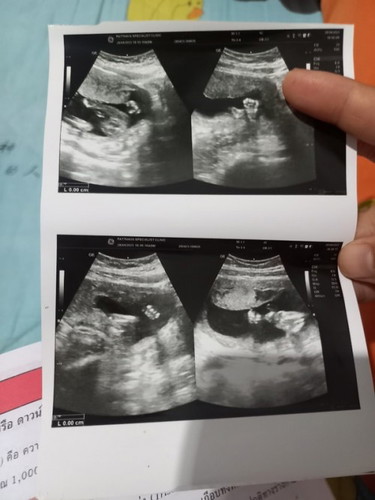

เพศลูกเพศอะไรพอจะทราบมั้ยคะ 19สัปดาห์2วันค่ะเเม่ๆพอจะทราบมั้ยคะว่าผู้หญิงหรือผู้ชาย พอดีหมอบอกน้องหุบขาไว้ค่ะ

ถ้าหุบก็ไม่เห็นค่ะ